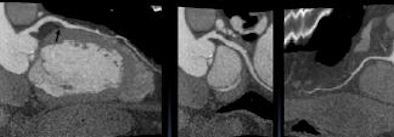

![]() |

| With one-beat scanning at 320-slice CT, contrast enhancement is more homogeneous and most artifacts are eliminated. |

| By shortening the scan time to 350 msec, the duration of peak enhancement can be shortened and the contrast dose reduced from 80-100 cc to 50-60 cc for a typical coronary CTA exam. |